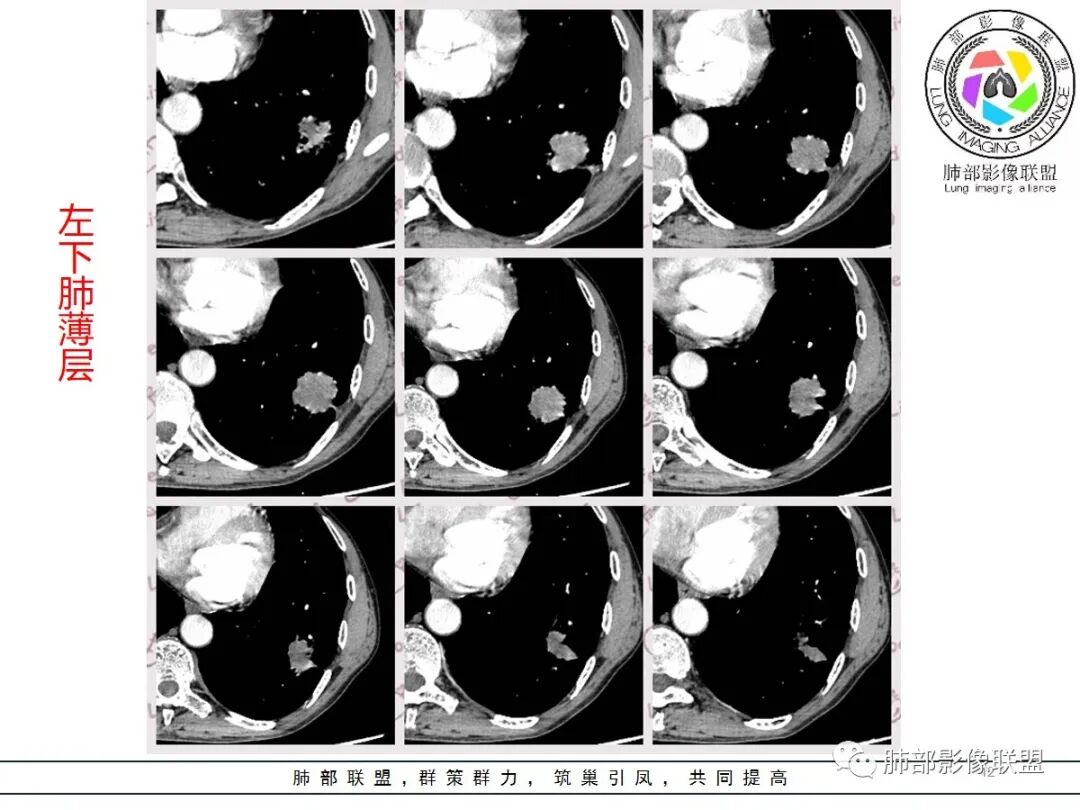

临床病史很长,背痛9年可能与左侧胸膜炎有关。两上肺陈旧性结核伴肺气肿没有问题。左下肺病灶,分叶毛刺、胸膜凹陷、指状凸起,增强轻度强化,腺癌问题不大。右侧附加题有些困难,病灶内血管显影,不像结核的表现,先把结核否掉?鳞癌和慢性脓肿的鉴别:支持良性的征像,低密度区内也有细小血管影,不像鳞癌坏死?与胸膜关系整体还是比较和谐,边缘还算光整,毛刺都在远端,不支持慢性脓肿的的地方,周围支气管管壁都很干净。恶性征像,与支气管的关系图片给的不够。坏死边缘不光整,有些浅分叶。总体,我觉得坏死区血管的存在更有价值,验证一下,右侧首先考虑慢性脓肿。

老年男性,结核、慢性病史,肺气肿背景,右肺胸膜下肿块影,边界清晰,边缘膨隆,中度环形强化,内见边界清晰坏死区,并见部分强化小血管,鳞癌破坏力强,而且病灶一侧支气管受推移,首先考虑右肺结核,鉴别鳞癌,左肺考虑腺癌,胸膜牵拉,膨隆生长,边缘毛刺样,潜在分叶。

小兜:

老年男性,既往肺结核病史。肺气肿背景,可见钙化灶及条索影。右肺下叶胸膜类圆形占位,边界清晰,内部可见边界清晰的坏死区,轻度强化,考虑为结核可能;左肺下叶结节,可见分叶,毛刺,胸膜牵拉,增强可见强化,考虑为恶性,腺癌可能。

右肺增强有强化,湖泊样坏死

4.右侧坏死明显,内部囊变坏死边缘部分清楚、部分不清

今天晨读我觉得最有特征性的就是那个强化,环状强化,周围强化比较明显的是癌,血供丰富,中间应该是肉瘤粘液变性,而且边界比较清楚,这个也算肉瘤样癌比较有特征性的,其他的跟其他恶性确实不好鉴别

主要征象:病灶分叶不明显、较光整,局部胸膜栽赃,支气管门口堵塞,有推移迹象;增强后坏死明显,内部囊变坏死边缘部分清楚、部分不清楚,病灶内可见血管,局部稍毛糙,实性部分强化较明显,总体考虑恶性病变。一部分征象指向鳞癌(支气管截断、坏死较多,病灶内血管破坏),但又有肉瘤的一些特点(病灶较大,缺乏分叶,坏死边界清晰),要考虑到肉瘤样癌。

3、本病好发于60岁以上的老年男性,多数有吸烟史。周围型多于中央型,病灶边缘较清楚,多数光整圆钝,部分可见浅分叶,少数有毛刺,无胸膜凹陷征出现。CT平扫时呈软组织密度,较小的肿块密度较均匀,肿块较大时中央常出现坏死。增强扫描肿块多呈斑片状不均匀强化,而肿瘤周边厚薄不均的囊壁样强化较具特征性。周围型多数位于胸膜下,常常侵犯胸膜或胸壁。